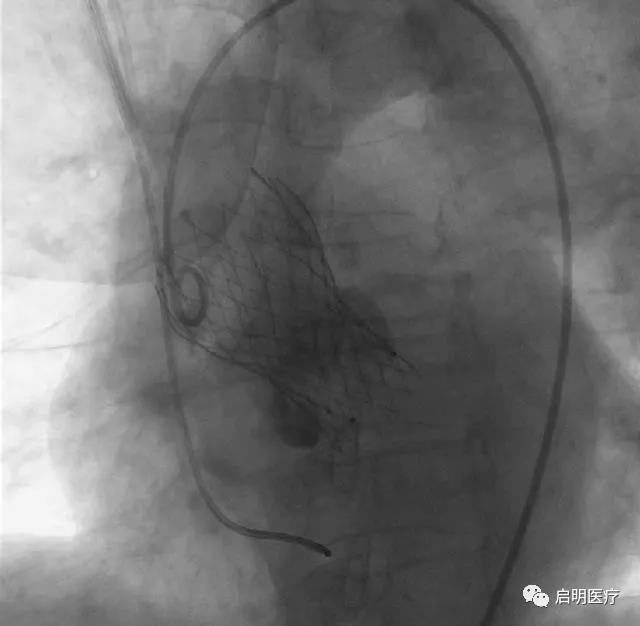

2017年11月23日,VenusA Plus可回收瓣膜系统首例临床应用在浙江大学医学院附属第二医院成功进行。

“释放、位置完美、输送系统撤出体外,VenusA Plus可回收瓣膜系统首例临床应用成功!”浙江大学医学院附属第二医院王建安教授宣布。这标志着启明医疗又攻克了一个经导管主动脉瓣膜置换术(TAVR)的技术难题,成为中国首家具有可回收介入心脏瓣膜系统的企业。

患者,76岁女性,诊断为:主动脉瓣重度狭窄,外科手术高危(STS 13.8%)。经浙医二院心脏团队讨论,该患者的解剖结构特点为二叶式主动脉瓣畸形、钙化不对称,瓣膜植入过程中移位的可能性大,手术难度高,适用于可回收系统。

可回收系统允许瓣膜在释放后收回重新定位,可避免瓣膜植入位置不佳及型号偏差引起的不良事件,如:瓣膜移位、重度瓣周漏、影响二尖瓣工作、压迫传导束造成高度房室传导阻滞等,同时也降低了手术的难度,有利于TAVR技术的推广和应用。